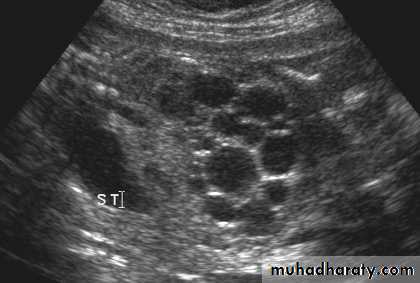

Both kidneys replaced by large no. of cysts of variable size which make the kidney of large size.

The cysts contain clear fluid but sometimes blood.

The cysts progressively increase in size causing pressure atrophy of the renal parenchyma and pressing the ureter.

U/S, IVU, CT scan, MRI